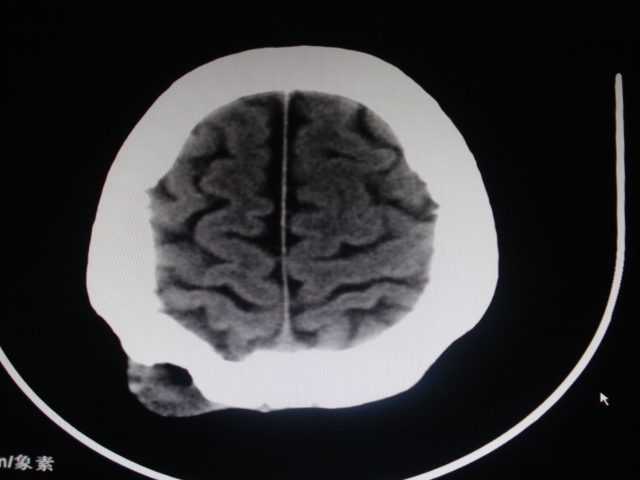

男性,48岁。发现右顶部包块一月余,质软有轻压痛。

其余没问题的层面我没有发上来,请教各位老师,可以考虑嗜酸性肉芽肿吗?